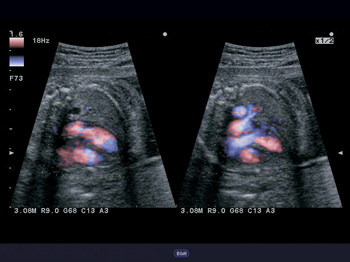

- Функция STIC: исследование сердца плода в режиме объёмной визуализации

- Функция STIC Color

Объемная визуализация сердца плода. Эта впечатляющая функция исследования сердца плода основана на достижениях технологии 4D и связана с пространственно-временной корреляцией получаемого вами изображения. Теперь вы сможете сохранять полученные данные для

Автоматическое измерение основных параметров биометрии плода в акушерстве. Удобная в использовании функция данного УЗ аппарата позволит вам с большей эффективностью определить и выявить возможные отклонения при наблюдении за развитием плода во время берем

Автоматический расчет воротникового пространства. Специальная функция поможет вам провести более точное исследование накопления жидкости в воротниковом пространстве плода при текущей беременности матери. Это позволит специалистам минимизировать риски врач